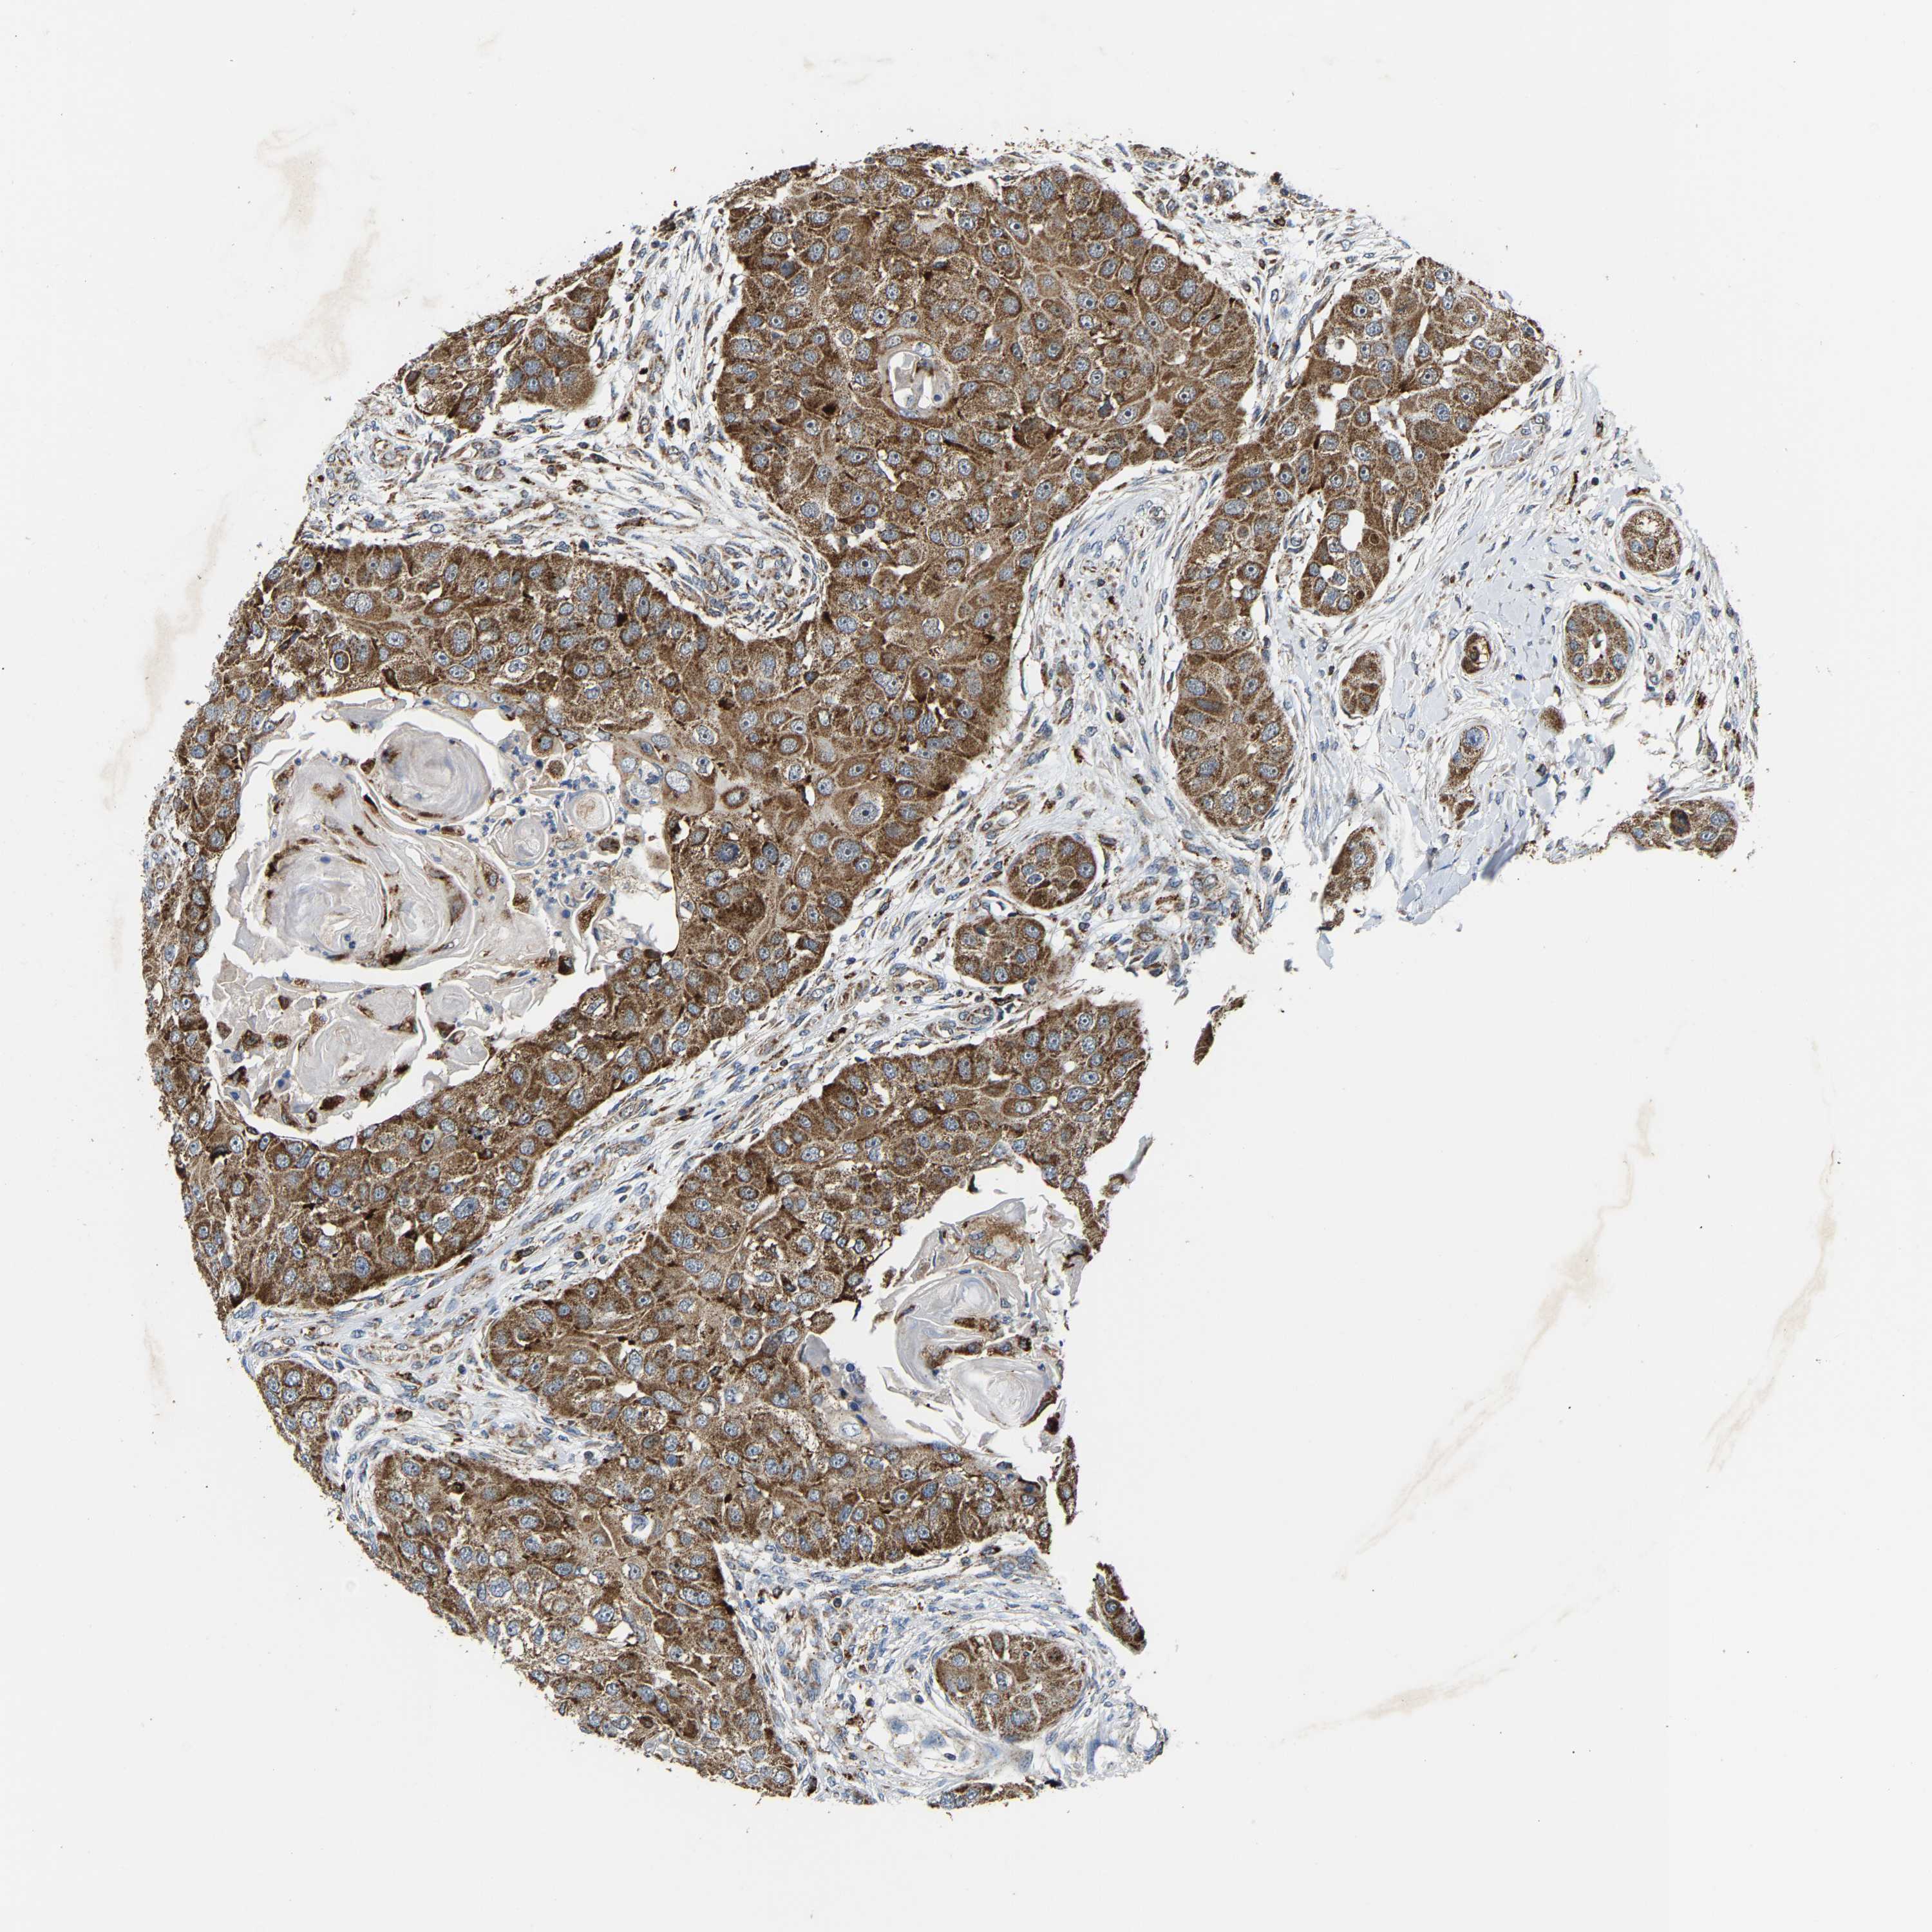

HEAD AND NECK CANCER - Protein expressioni

A mouse-over function shows sample information and annotation data. Click on an image to view it in a full screen mode. Samples can be filtered based on level of antibody staining by selecting one or several of the following categories: high, medium, low and not detected. The assay and annotation is described here.

Note that samples used for immunohistochemistry by the Human Protein Atlas do not correspond to samples in the TCGA dataset.

Antibody stainingi

Antibody staining in the annotated cell types in the current human tissue is reported as not detected, low, medium, or high, based on conventional immunohistochemistry profiling in selected tissues. This score is based on the combination of the staining intensity and fraction of stained cells.

Each image is clickable and will lead to virtual microscopy that enables deeper exploration of all samples and also displays staining intensity scores, fraction scores and subcellular localization as well as patient and tissue information for each sample.

Antibody HPA020266

Antibody HPA020268

Staining

High

Medium

Low

Not detected

Intensity

Strong

Moderate

Weak

Negative

Quantity

>75%

75%-25%

<25%

None

Location

Nuclear

Cytoplasmic/membranous

Cytoplasmic/membranous,nuclear

Squamous cell carcinoma, NOS

Squamous cell carcinoma, metastatic, NOS

Adenocarcinoma, NOS